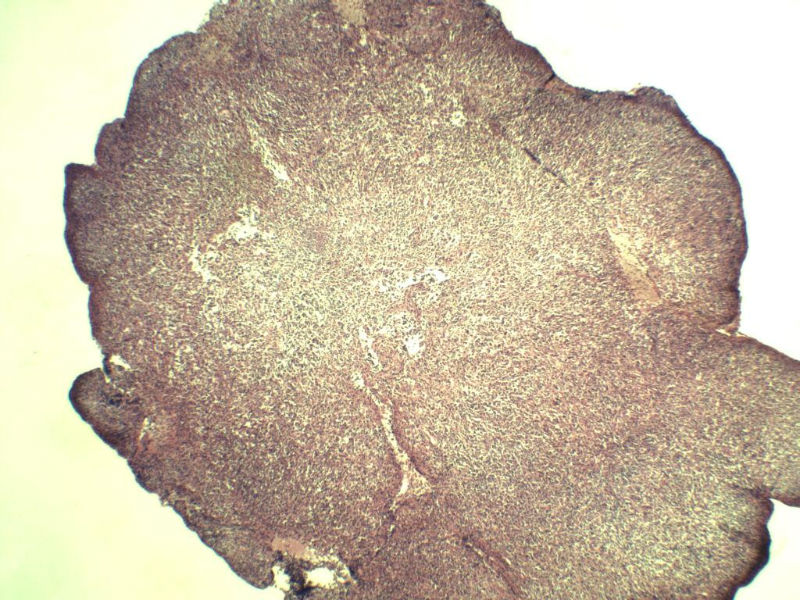

男,38岁,腹股沟 多枚淋巴结活检  直径 0.2-0.5 请各位老师看看 是什么 谢谢了!

"畏寒,发热咳嗽1年,加重伴腹部疼痛2月" 2月前患者感腹部疼痛不适伴大便呈稀大便,量不详,伴腰骶部疼痛,胸片:纵膈及右肺门多发性淋巴结肿大,进一步完善胸部CT:右肺及中叶病变,纵膈及肺门多发淋巴结肿大,结核性可能,脾脏增大,PPD(-),1个月来患者出现中上腹食欲不振,体重进行性消瘦,全身疲乏无力,3天前到医学院就诊,腹部B超:右肝囊肿,胆囊壁毛糙,脾大,胰周多个减弱回声,淋巴结不能除外,腹水,血常规示:WBC16.36x109 /L,N%14.25%,RBC2.63x1012/L ,HGB 66g/L 。右侧腋窝及腹股沟可扪及多枚淋巴结,压痛,无明显粘连。

腹股沟 多枚淋巴结活检图4

淋巴结正常结构破坏,可见大的异型细胞,上皮样或梭形,恶性肿瘤,依据病史,首先考虑淋巴造血系统疾病,大中小细胞混杂,大细胞多,形态多样,可见多核瘤细胞,除以上考虑外需鉴别间变大、组织细胞肉瘤、指状突/树突细胞肿瘤、HL等,还需排除肉瘤或癌转移,尽管病人年轻,加上ALK、CK、S-100、CD1a。

薄切淋巴结,调好采图色差,图片不是很清楚。